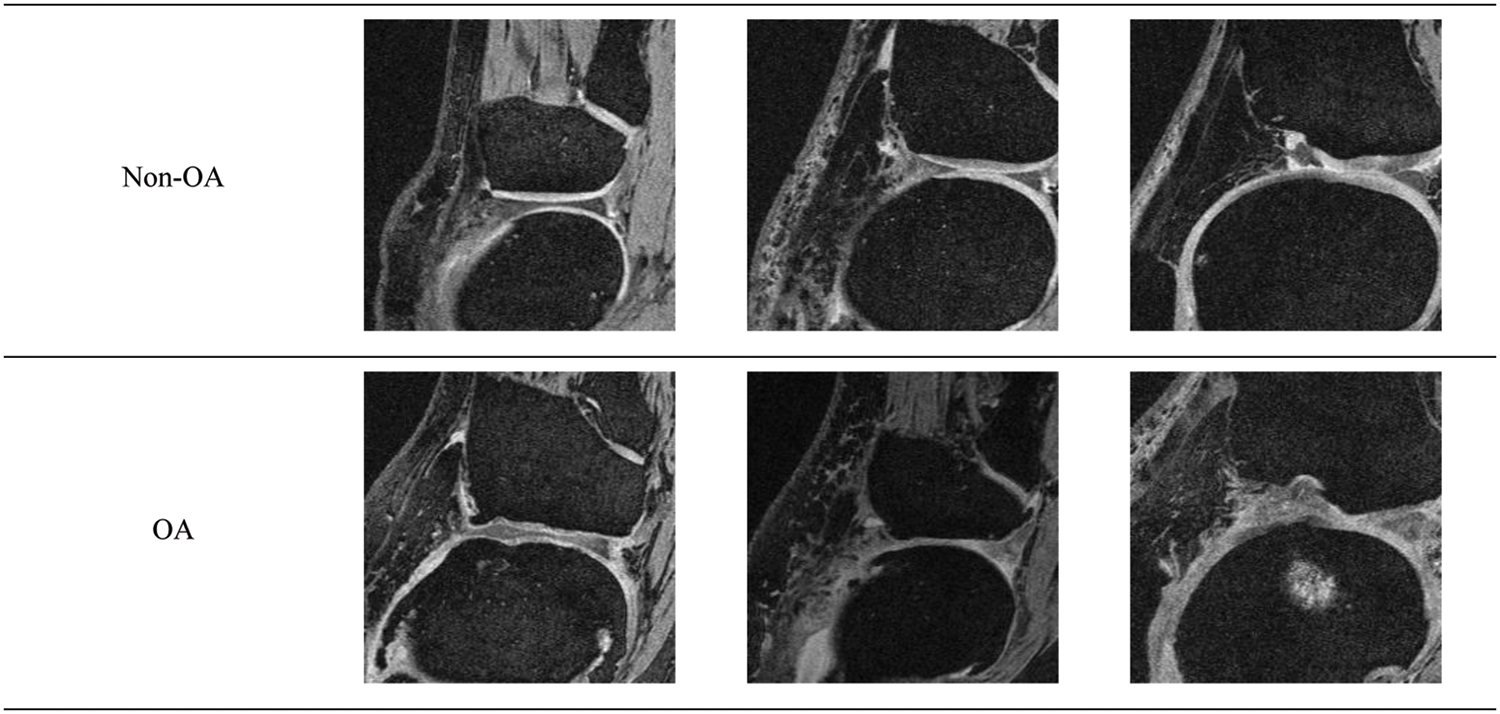

Examples of various imaging technologies used in osteoarthritis (OA)... Download Scientific Magnetic Resonance Therapy For Knee Osteoarthritis Mr imaging is able to detect morphologic and compositional alterations in knee cartilage; In terms of duration of treatment, four studies suggested treatment for nine consecutive days, two for five days and one study reported. An magnetic resonance imaging (mri) uses radio waves and a strong magnetic field to produce detailed images of bone and. A general overview of the. Magnetic Resonance Therapy For Knee Osteoarthritis.